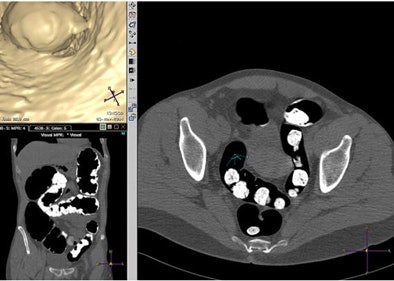

![]() |

| Axial multiplanar reformatted coronal and endoluminal 3D images show subjective evaluation in four different patients with various grades of fecal tagging. Above, in 51-year-old woman with history of colorectal polyps, reviewer evaluated fecal tagging as good. Image republished with permission of the American Roentgen Ray Society. Jensch S, de Vries AH, Pot D, et al. Image quality and patient acceptance of four regimens with different amounts of mild laxatives for CT colonography. AJR. 2008;191(1):158-167. |